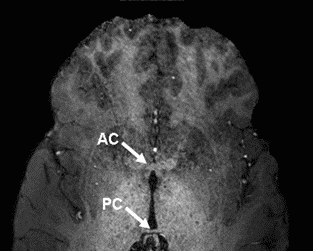

1. Re-open set01_axial_crop in MRIcro and scroll through the slices until you see the anterior commissure, see below.

3. Select the Crossbars option and click on the Anterior Commissure (AC), ensuring the location is correct in all three planes.

4. Note the X, Y, Z voxel coordinate, and type them into the Origin (vxl) location in MRIcro, near the top left of the window.